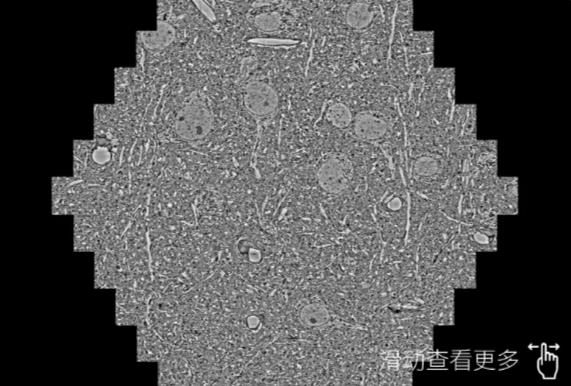

鼠脑切片。左图使用静海蔡司静海扫描电镜MultiSEM706对165μmx143pm面积区域成像,耗时仅需1.5秒。右图为鼠脑切片中30μm区域放大效果。样品由芝加哥大学B.Kasthuri提供。

使用蔡司高速静海扫描电镜MultiSEM对1mm²人脑皮层组织进行高分辨成像,并对其中的各种细胞结构进行三维重构分析。左图展示了2x3mm²组织平面中锥体神经元的三维重构效果。右图显示了局部体积神经元三维重构。图像由哈佛大学chtman实验室提供,渲染图由D. Berger 制作。